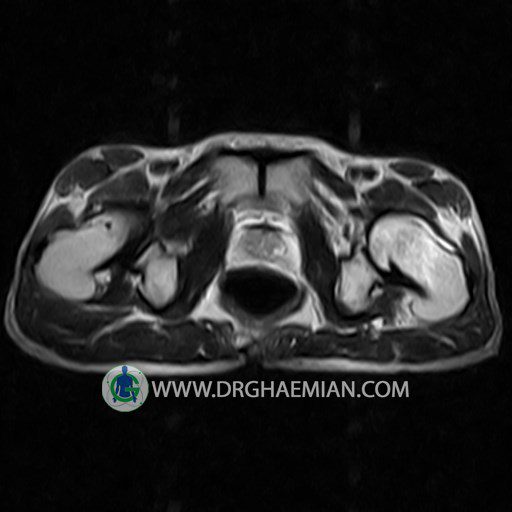

پزشکان اغلب از تصویربرداری ام آر آی برای تشخیص و درمان عارضه های پزشکی که فقط با استفاده از اشعه ایکس یا میدان مغناطیسی و امواج رادیویی قابل مشاهده است، استفاده می کنند. دستگاه ام آر آی تصاویر دقیق از ساختار های داخلی بدن ایجاد می کند. در این کیس استئومیلیت لگن، آتروز و سنیویت دیده می شود.

HIP JOINT MRI

( without contrast )

Technique : coronal STIR , coronal T2 , Axial T1 , axial T2 .

REPORT:

The femoral heads and acetabula are normal shape , signal intensity and the femoral heads are well covered by the acetabular margins .

The joint spaces are of normal width without fluid collection .

The articular surfaces are smooth and congruent and show normal cortical thickness .

Each femoral shaft has normal margins and contains a normal bone marrow signal .

The imaged muscles and the lesser pelvis show no abnormalities .

– Heterogeneous signal change (high T2/STIR , low T1) in proximal metaepiphysis of left femur without articular surface irregularity suggestive for bone bruise (stress fracture?), osteomyelitis & arthritis and marrow infiltration (less probable)

– Left hip joint effusion suggestive for synovitis

are seen.

COMMENT: Clinical correlation and MRI with contrast are recommended.